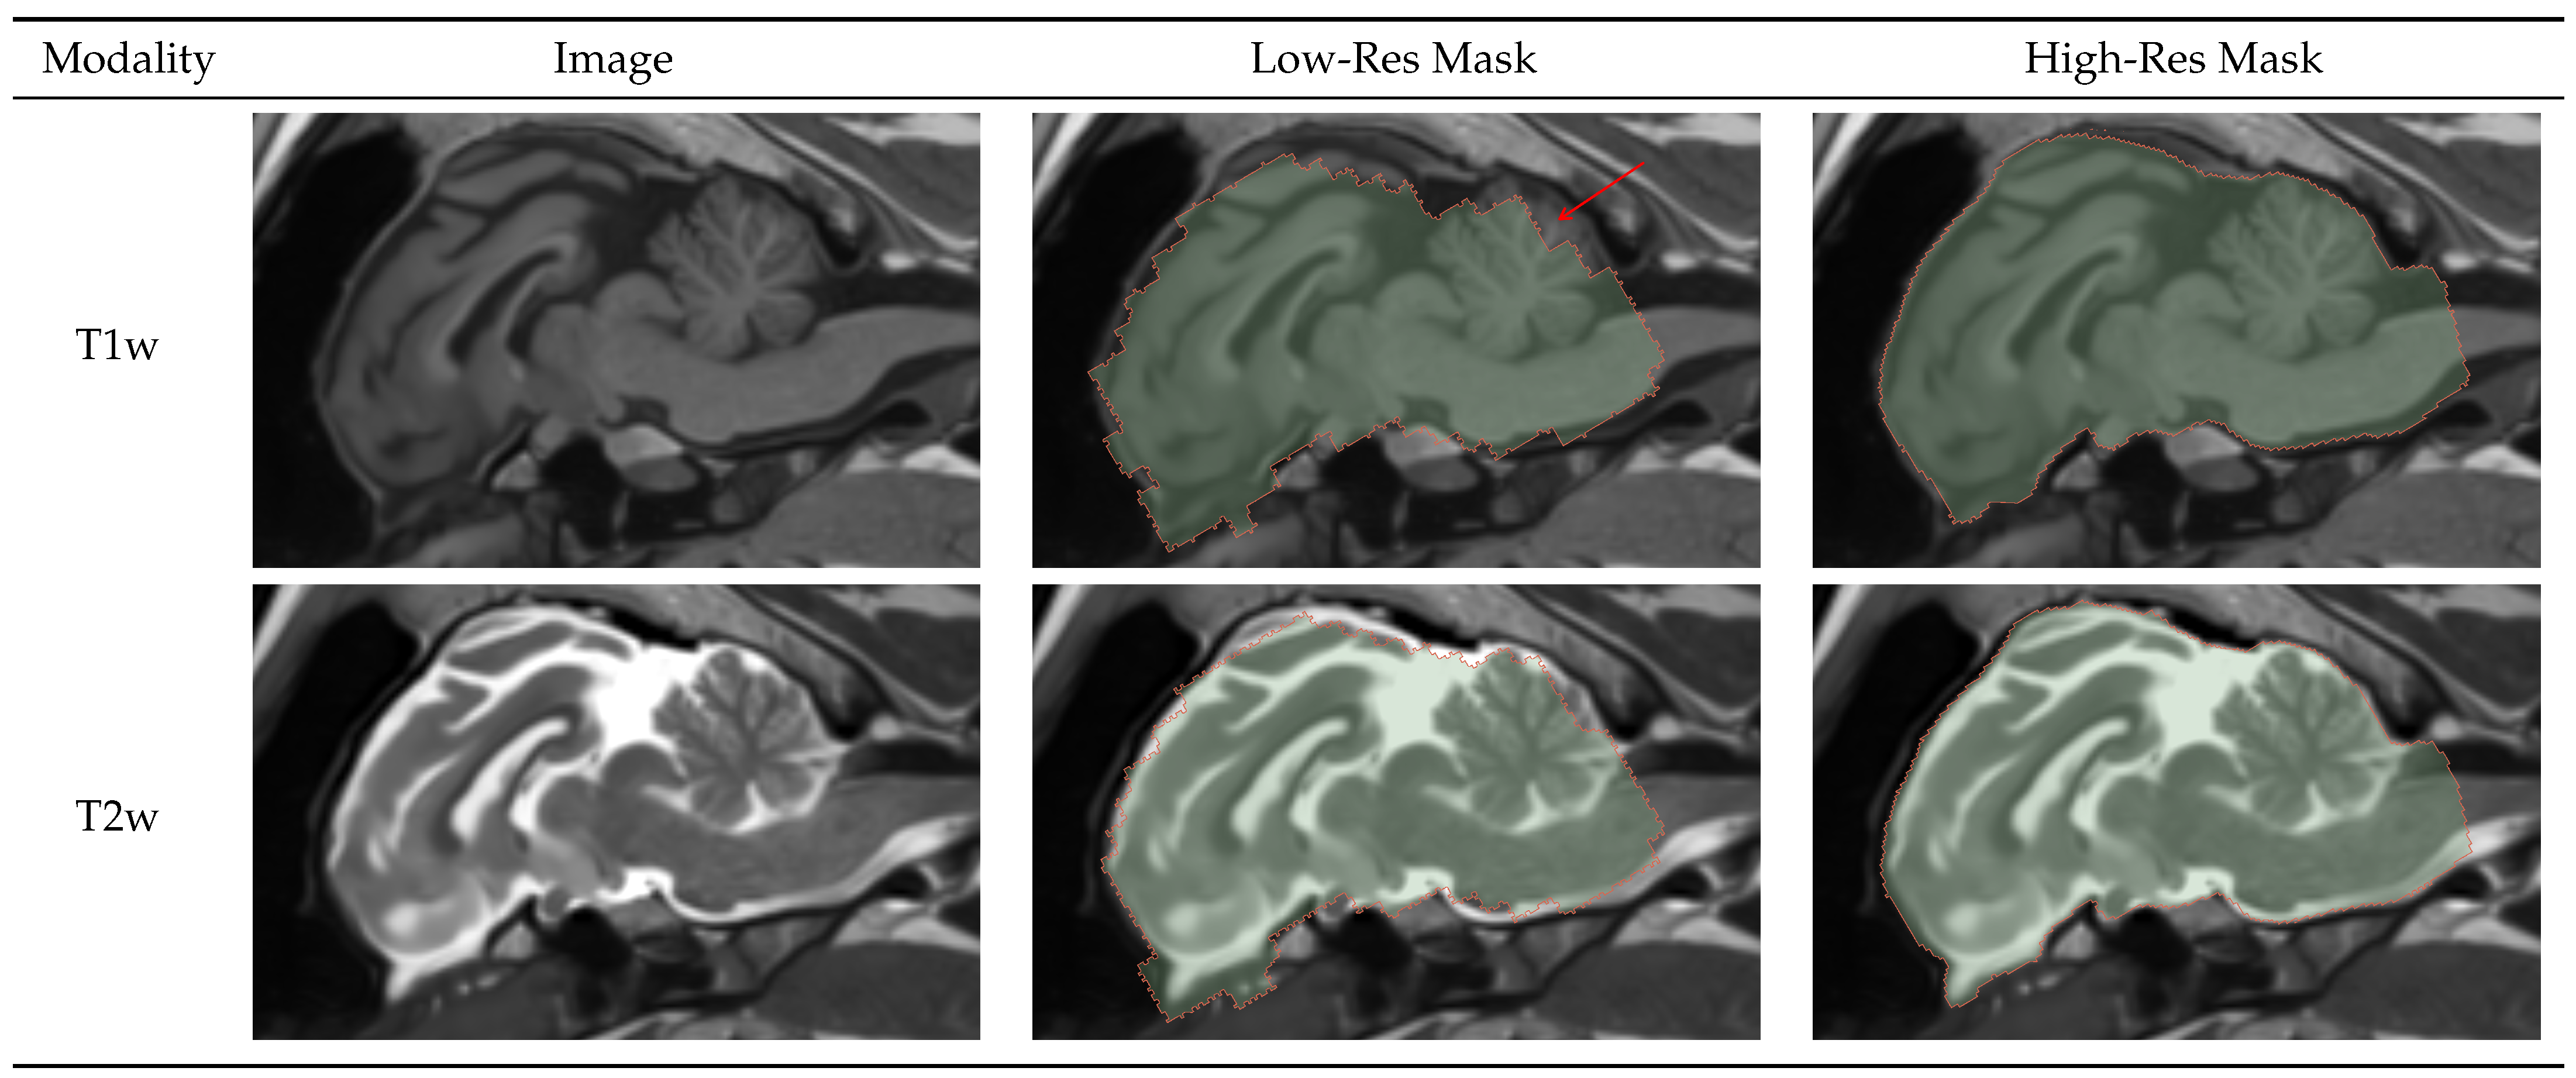

4.1.1. Brainmask

Figure 2 shows a 2D sagittal slice of the T1w and T2w images and their corresponding low- and high-resolution brainmasks. We can see that the low-resolution mask had very coarse boundaries and mistakes, such as missed parts of the cerebellum, indicated by the red arrow. Although the accuracy of the low-resolution mask was much worse than that of the high-resolution mask, it robustly found the position of the brain. This allows for accurate image cropping and the generation of a highly accurate high-resolution mask.

Figure 2.

Result visualization for low and high-resolution brainmask models on T1 and T2 weighted images. The low-resolution model robustly detected the brain from a large volume, allowing for image cropping and generating an accurate high-resolution brainmask.